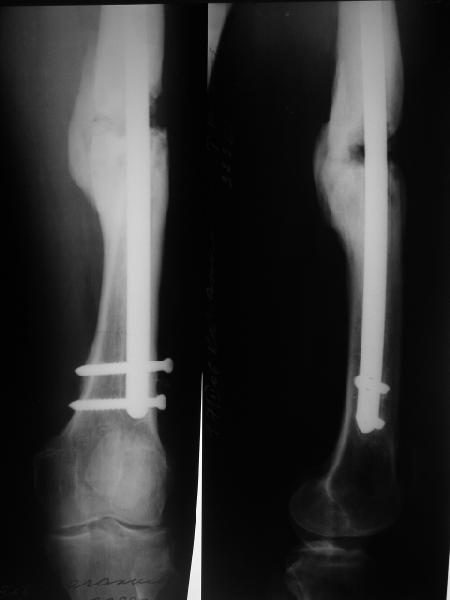

В приложении снимки бедра - с такой картинкой пациентка ходит, не хромает, работает инженером 3,5 года после операции с первых дней, хотя еще и инсулинозависимый диабет.

У нас есть все же сомнения, насколько он "тугой". Наличие хоть и нестабильной но все же фиксации пластиной, маскирующей степень подвижности; сочетание на рентгенограммах зон гиперостоза с зонами лизиса не дает четкой уверенности ни в том, что это тугой ложный сустав в классическом понимании, ни что это истинно атрофическая ситуация. А чем сейчас можно быть уверенным? Вот потому и одолевают сомнения.

Наш пациент имеет рост 2 м и вес 120 кг, при этом он не выглядит полным. Так что не очень хочется надеяться только на гвоздь, хотелось бы и репаративные процессы обеспечить.